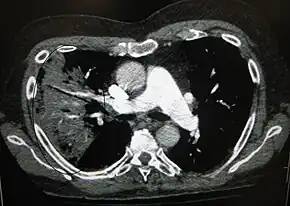

A black-and-white image shows the internal organs in cross-section as generated by CT. Where one would expect black on the left, one sees a whiter area with black sticks through it.

CT of the chest demonstrating right-side pneumonia (left side of the image)

A chest radiograph is frequently used in diagnosis.[20] In people with mild disease, imaging is needed only in those with potential complications, those not having improved with treatment, or those in which the cause is uncertain.[20][60] If a person is sufficiently sick to require hospitalization, a chest radiograph is recommended.[60] Findings do not always match the severity of disease and do not reliably separate between bacterial infection and viral infection.[20]

X-ray presentations of pneumonia may be classified as lobar pneumonia, bronchopneumonia, lobular pneumonia, and interstitial pneumonia.[66] Bacterial, community-acquired pneumonia classically show lung consolidation of one lung segmental lobe, which is known as lobar pneumonia.[34] However, findings may vary, and other patterns are common in other types of pneumonia.[34] Aspiration pneumonia may present with bilateral opacities primarily in the bases of the lungs and on the right side.[34] Radiographs of viral pneumonia may appear normal, appear hyper-inflated, have bilateral patchy areas, or present similar to bacterial pneumonia with lobar consolidation.[34] Radiologic findings may not be present in the early stages of the disease, especially in the presence of dehydration, or may be difficult to interpret in the obese or those with a history of lung disease.[21] Complications such as pleural effusion may also be found on chest radiographs. Laterolateral chest radiograph can increase the diagnostic accuracy of lung consolidation and pleural effusion.[33]

A CT scan can give additional information in indeterminate cases.[34] CT scans can also provide more details in those with an unclear chest radiograph (for example occult pneumonia in chronic obstructive pulmonary disease) and is able to exclude pulmonary embolism and fungal pneumonia and detecting lung abscess in those who are not responding to treatments.[33] However, CT scan is more expensive, has a higher dose of radiation, and cannot be done at bedside.[33]